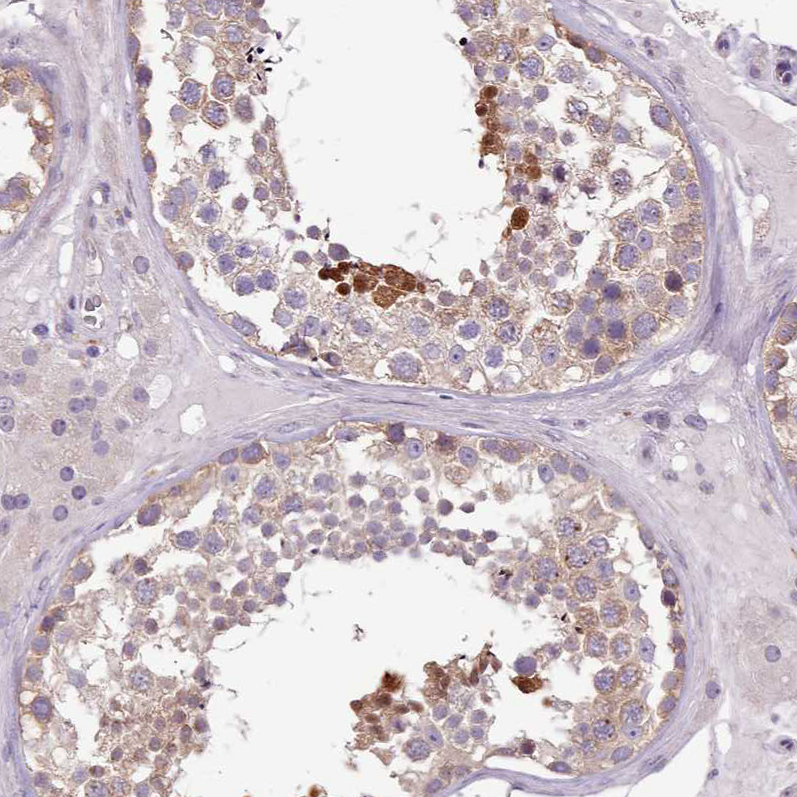

Immunohistochemical staining of human testis shows strong nuclear positivity in a subset of cells in seminiferous ducts.